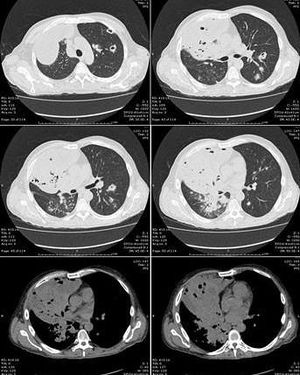

This chest CT Scan shows cavitary formation caused by the nocardia infection.Nocardiosis is an infection caused by fungus like bacteria called nocardia. It can produce two types of infections either pulmonary or cutaneous. In Pulmonary Nocardiosis there will cavitary formation that is sometimes misdiagnosed with TB, with Immunocompromised patients being in high risk. In Cutaneous Nocardiosis there will be cellulitis with abscess formation that is usually caused by traumatic implantation. Treatment of both types is Sulfonamides or TMP-SMX.